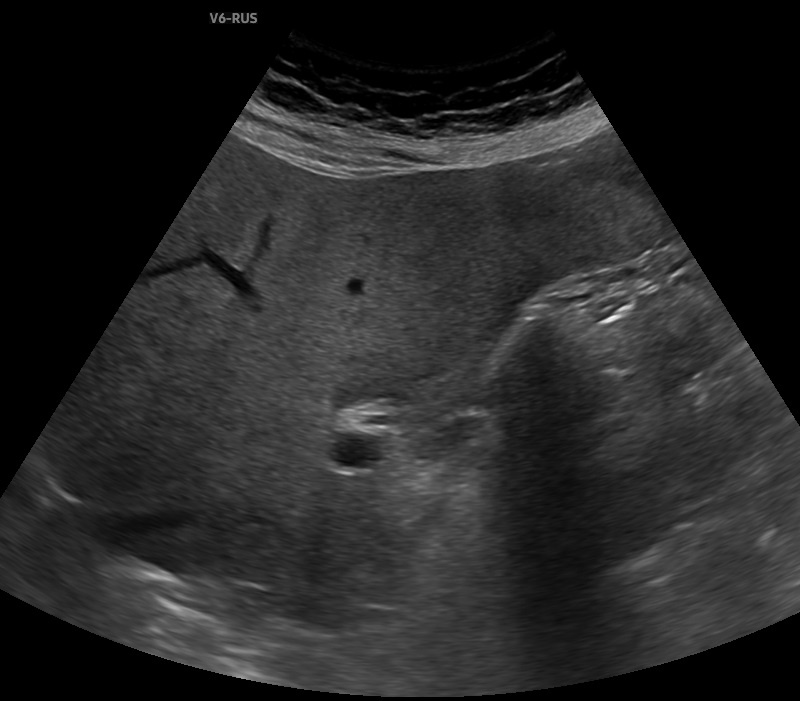

Рис. 0 Картинка из свободного доступа При выполнении ультразвукового исследования есть определенные правила, которые надо всегда помнить. Первое - всегда соблюдать методику исследования. Более половины всех ошибок возникают из-за нарушений методики. Второе - никогда не расслабляться. Даже если "случай" кажется простым и очевидным, нужно максимально внимательно всё изучить и рассмотреть. Именно поэтому всегда говорим о полипозиционном и полипроекционном исследовании. Особенности анатомии, аномалии, артефакты нередко могут нам "подложить свинью" и повести диагностический поиск по ложному пути, симулируя или маскируя патологию. Хочу продемонстрировать клинический случай из недавней практики. Пациентка 85 лет обратилась для ультразвукового исследования органов брюшной полости. Из жалоб - умеренные боли и дискомфорт в правой половине живота. Со слов - ранее выявляли камни в желчном пузыре. При ультразвуковом исследовании в зоне желчного пузыря определяется гиперэхогенная структура протяжен